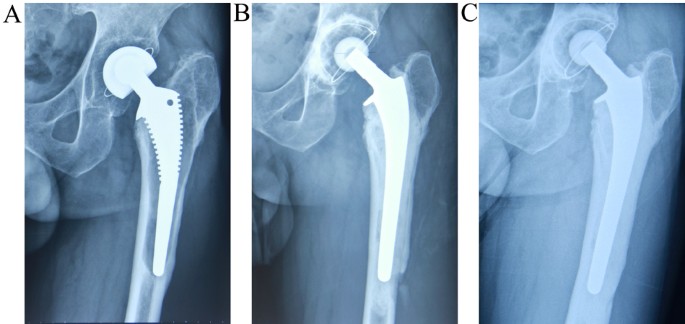

Implants and components used in revision procedures

Revision hip replacement surgery often requires specially designed implants to accommodate the unique challenges that can arise when a hip joint has already been operated on. These challenges may include bone loss, implant loosening, joint instability, or infection. Compared to primary hip replacements, revision implants are typically more robust and versatile, offering added fixation and support where standard implants may no longer be suitable.

Addressing bone loss, instability, and joint integrity

When the bone around the original implant has deteriorated or been damaged, specialised implants can help rebuild structural support. These may include:

• Longer stems to reach deeper into healthy bone and provide a more secure anchor

• Modular components that allow flexibility in tailoring the implant to your individual anatomy and bone quality

• Reinforcement devices or augments to fill bone defects and restore stability

• Dual mobility cups or constrained liners to reduce the risk of dislocation in cases of soft tissue laxity or instability

Careful implant selection for individual needs

At Melbourne Orthopaedic Clinic, your surgeon will thoroughly assess your hip through advanced imaging and clinical evaluation before selecting the most appropriate implant components. Every revision procedure is personalised, with the goal of restoring stability, relieving pain, and supporting long-term joint function.